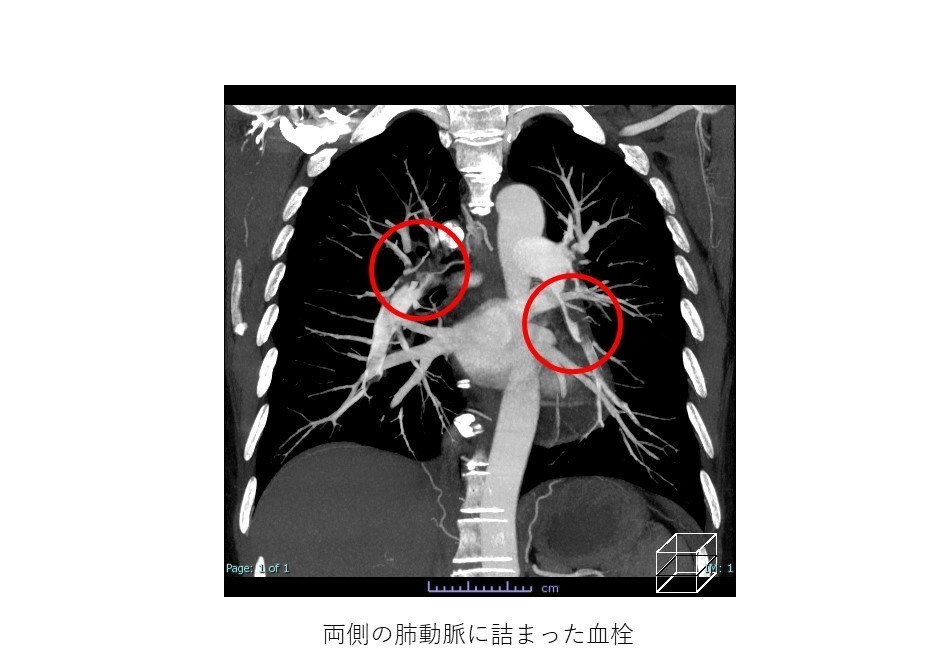

画像検査は、頸静脈内の血栓の存在を確認するために使用されます。頸静脈血栓症の診断に役立つ検査の 1 つは、ドップラー超音波検査です。

ドップラー超音波検査は、音波を使用して血球などの移動する物体の画像を作成する非侵襲的検査です。これにより、血液が血管内をどのように流れているかを医師に示すことができ、詰まりを特定するのに役立ちます。

頸静脈血栓症の診断には、次のような他の種類の画像検査も使用できます。